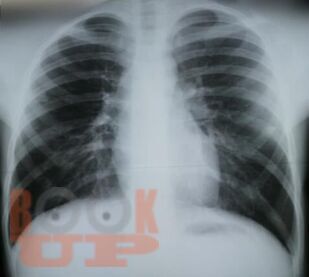

Учебное пособие составлено в соответствии с требованиями ФГОС ВО по специальностям 31.05.01 Лечебное дело и 31.05.02 Педиатрия, рабочей программы дисциплины «Фтизиатрия». В пособии представлена клиническая классификация туберкулеза, но сделан акцент на локализацию туберкулеза органов дыхания, иллюстрированная рентгенологическими снимками больных, лечившихся в КГБУЗ «Красноярском краевом противотуберкулезном

диспансере №1» с 1980-х г. по настоящее время, также даны определения различным формам туберкулеза органов дыхания.